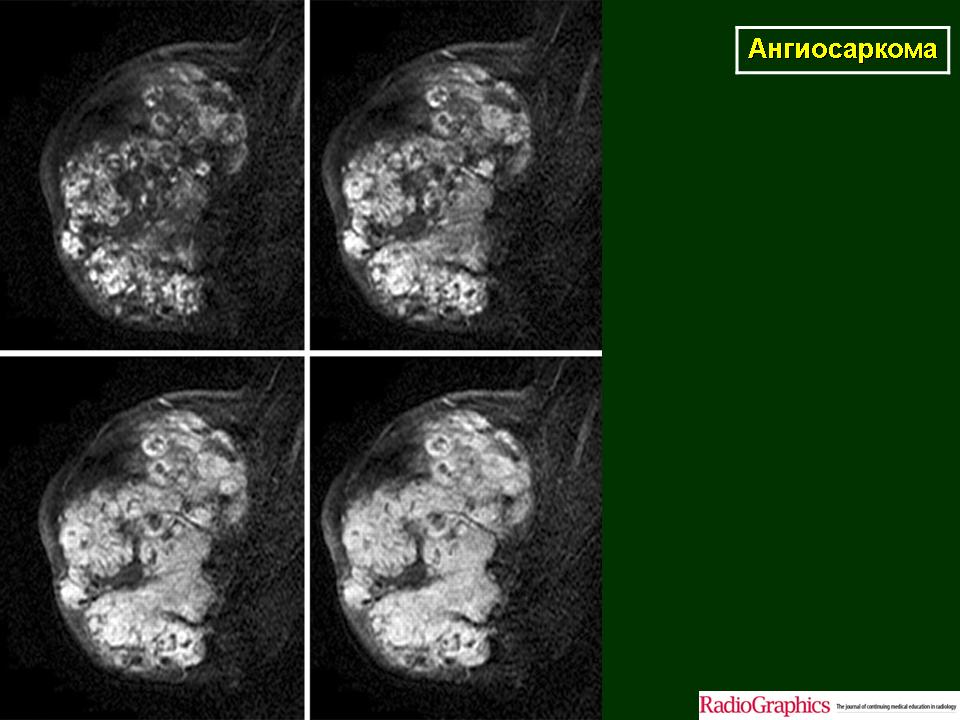

Молочная железа. Онк. Зл. Ангиосаркома. +

Ангиосаркома.